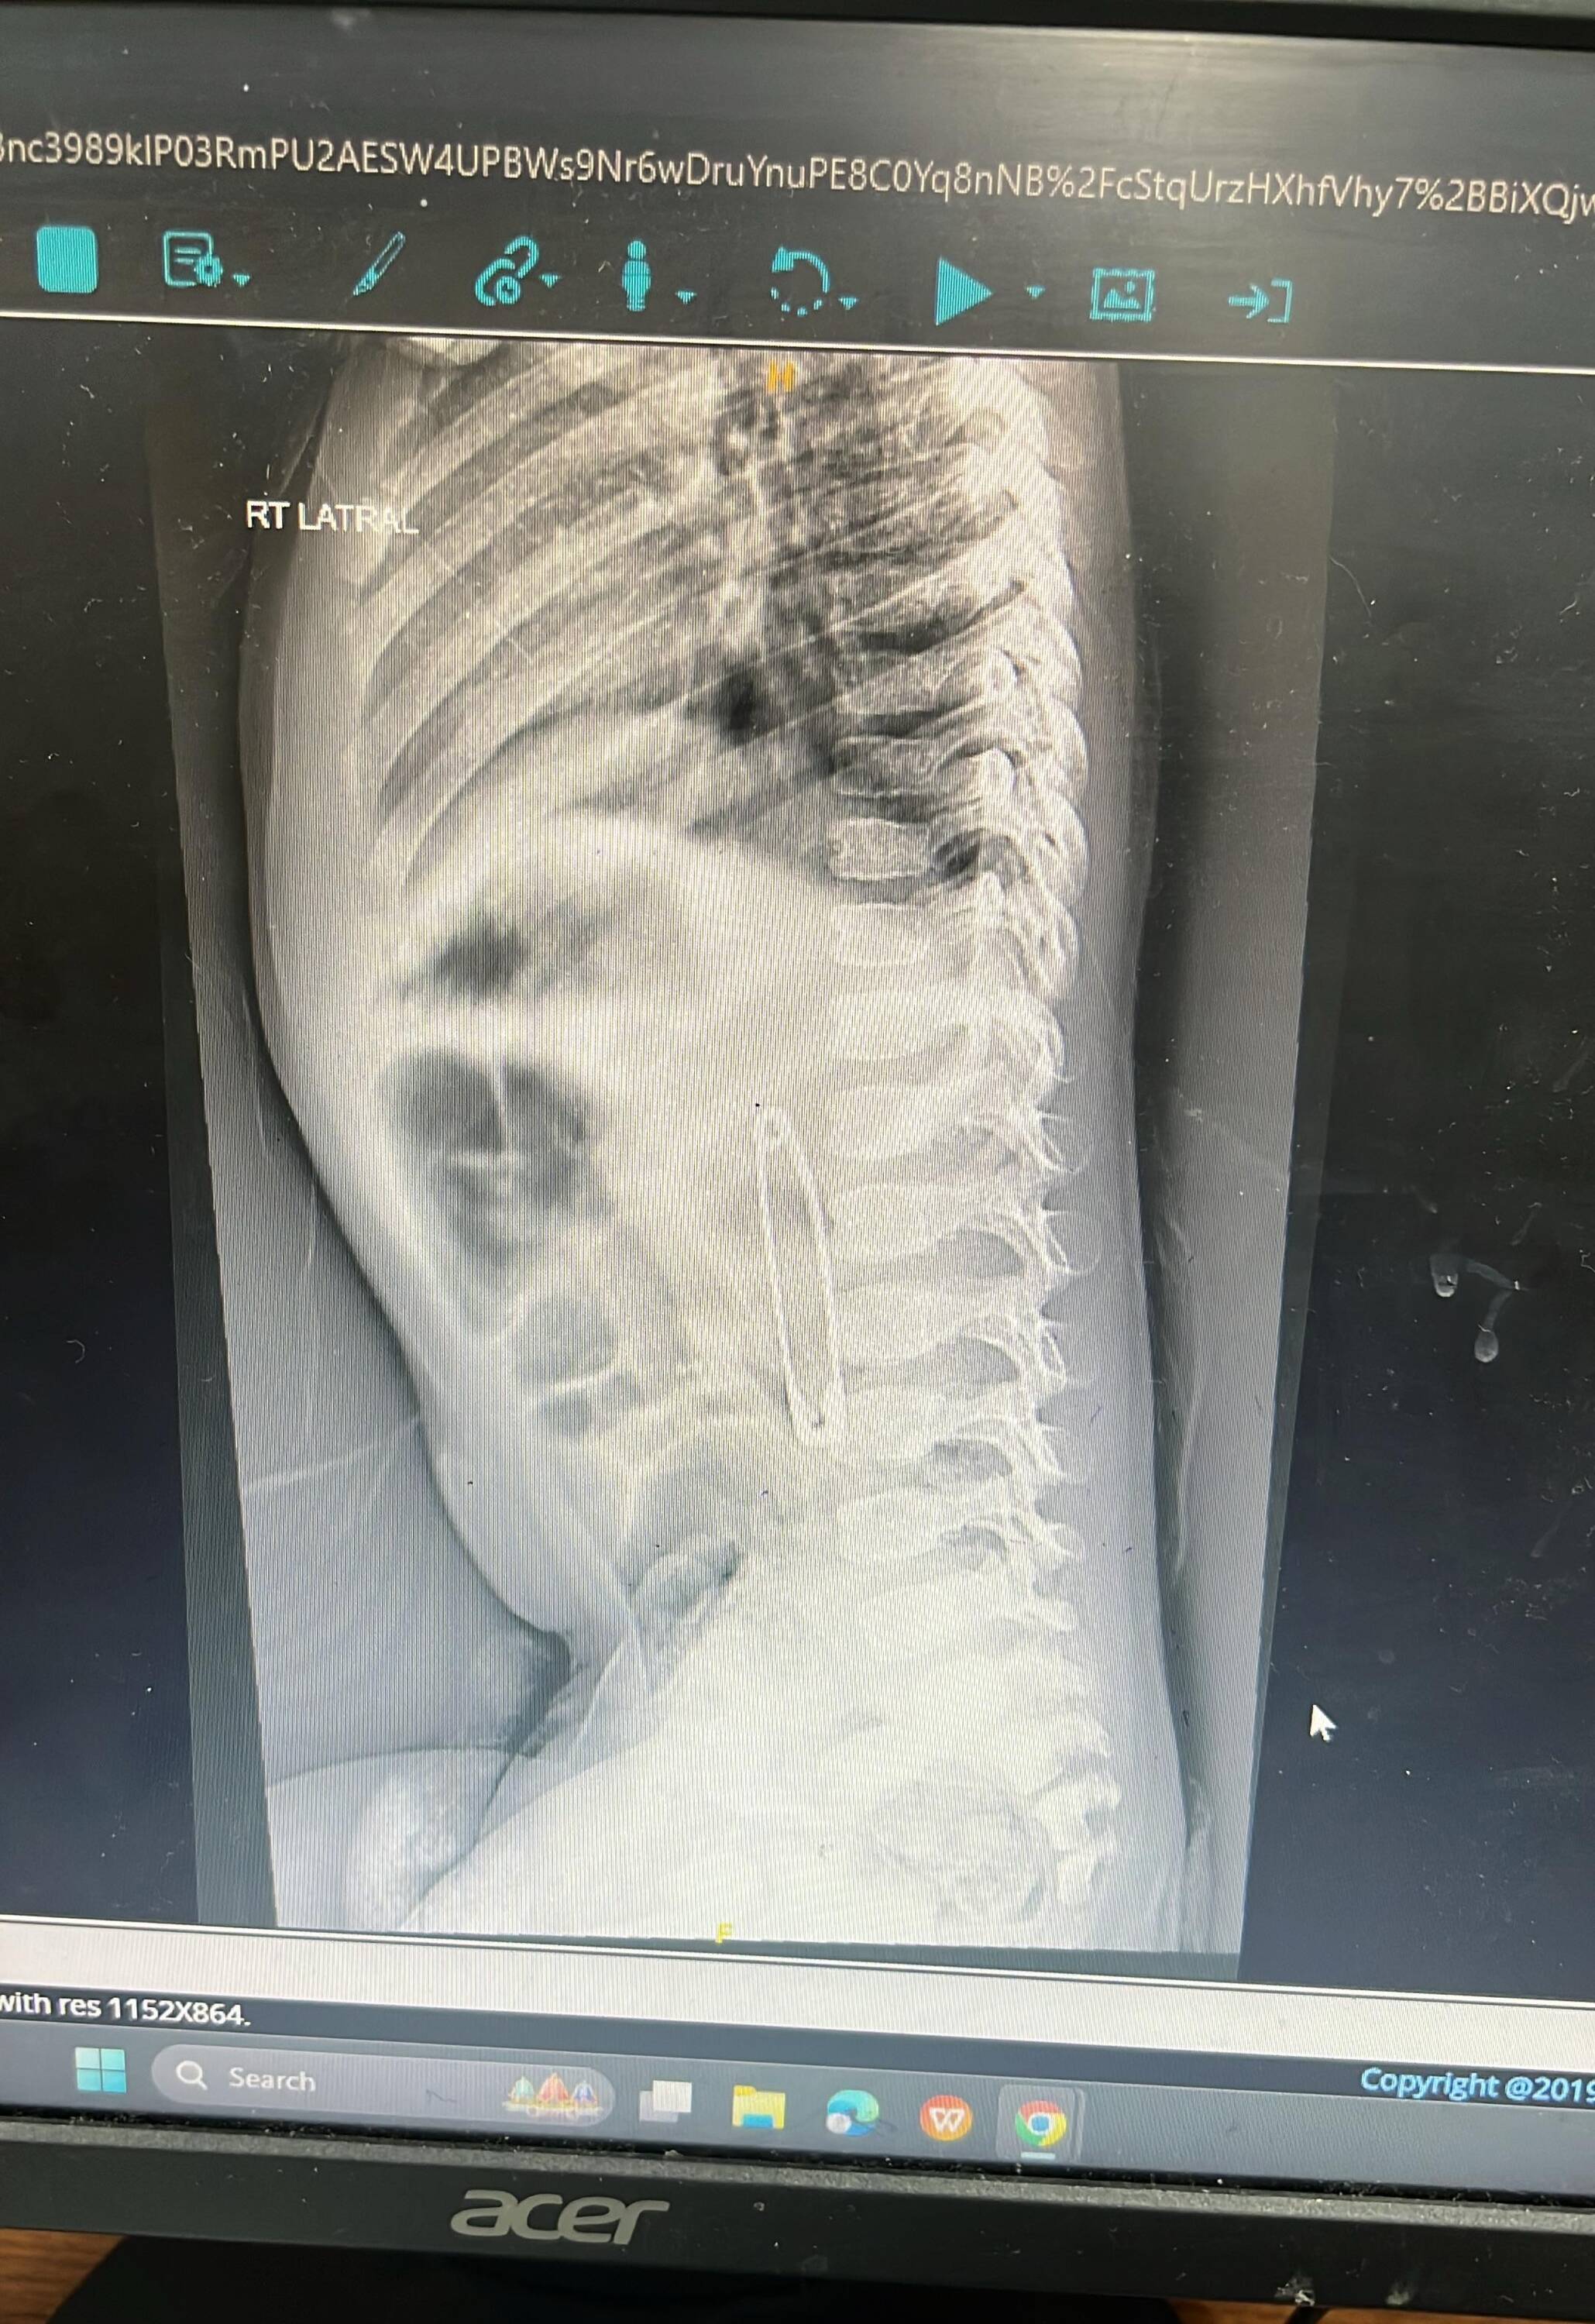

- X-ray confirmed the presence of a foreign metallic object (safety pin) in the gastrointestinal tract

- Diagnosis: Accidental ingestion of sharp metallic object โ safety pin